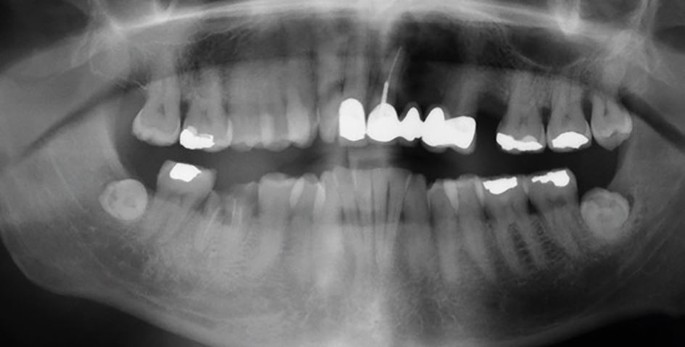

The introduction of a safe discharge network for the ongoing oral healthcare of patients who have completed management for head and neck cancers

Dental access remains a significant barrier to HNC patients. In addition to this, there is evidence…